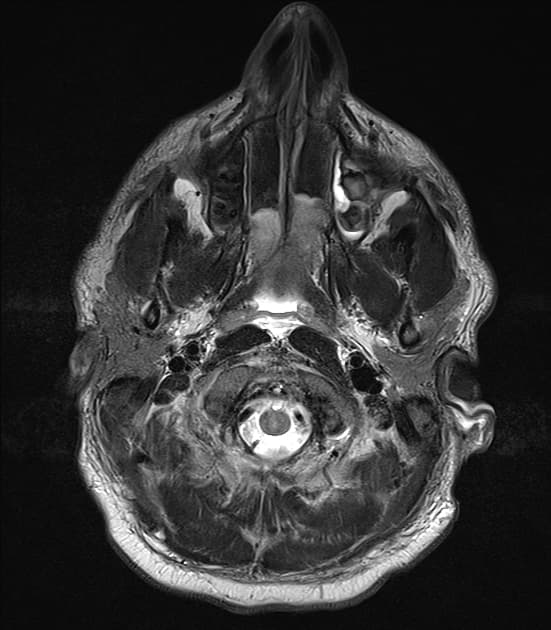

Chụp cộng hưởng từ (MRI) cho thấy các đặc điểm điển hình của bệnh xơ cứng rải rác. Ngoài ra, một số tổn thương có tín hiệu tăng trên hình ảnh T1 (T1 hyperintense).

Các phát hiện chính:

- Các tổn thương rải rác, dạng vệt hoặc hình tròn, tăng tín hiệu trên hình ảnh khuếch tán (diffusion-weighted imaging), khu trú chủ yếu ở vùng chất trắng quanh thất (periventricular white matter), chất trắng ở bán nguyệt (juxtacortical white matter), thân gai thị – giao thoa thị giác (optic radiation – optic chiasm), và thân não (brainstem) – phù hợp với đặc điểm của xơ cứng rải rác (multiple sclerosis).

- Thể chai (corpus callosum) có tổn thương dạng dải ngang (Dawson's fingers) – đặc trưng của xơ cứng rải rác (multiple sclerosis).

- Không có tổn thương màng não (leptomeningeal) hay ngấm thuốc viền (rim enhancement).

- Các não thất và khe não bình thường về kích thước, không thấy giãn não thất (hydrocephalus) hay xóa (rãnh não/bể não) (effacement).